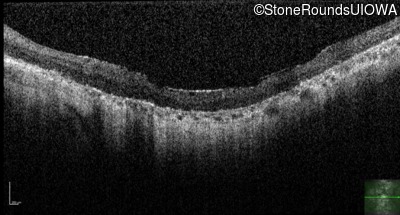

Optical Coherence Tomography - Left - Hand Motion sc

Exemplar / OCT Stack